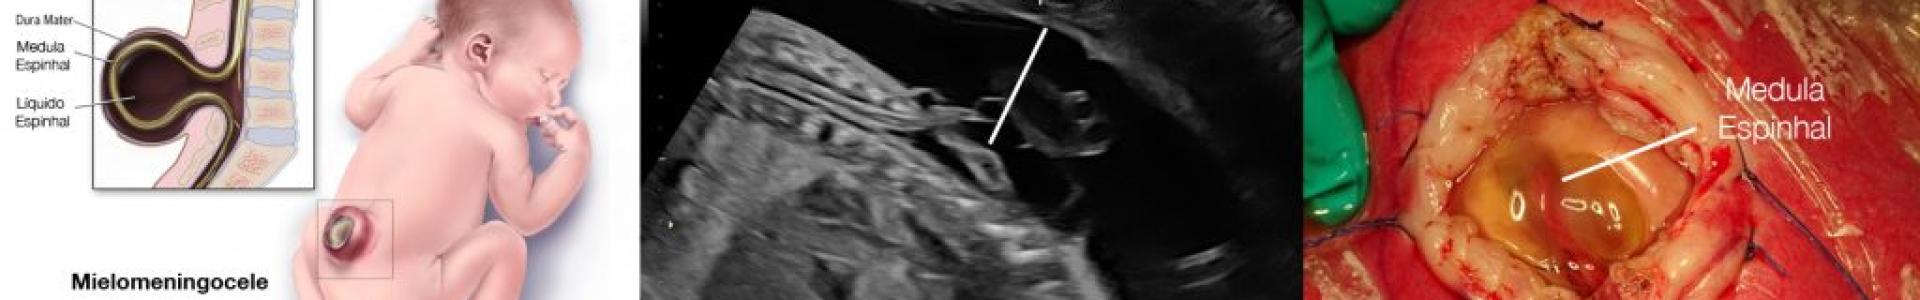

3. Mielomeningocele

- Forma mais grave e complexa.

- Protrusão da medula e meninges por uma falha na estrutura vertebral.

- Pode causar comprometimento motor parcial ou total, disfunções urinárias e intestinais, e hidrocefalia.

- Tratamento envolve cirurgia precoce e acompanhamento multidisciplinar.

Diagnóstico da espinha bífida

O diagnóstico é feito durante a gestação por ultrassonografia morfológica: